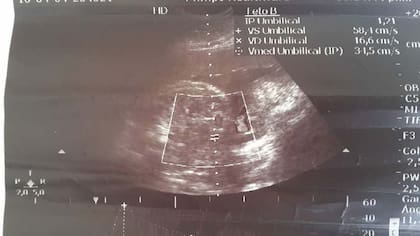

Durante la gestación, Juárez se hizo cuatro ecografías, tres en el mismo hospital y la restante en un sanatorio privado, en las que se constaba la presencia de dos fetos en el útero, con precisiones de peso estimativo, frecuencia cardíaca, longitud y cantidad de líquido amniótico.

En tanto, la segunda ecografía se realizó cuando ya cursaba el tercer trimestre de la gestación y se la practicó un médico privado de la ciudad de Alderetes, donde tuvo por primera vez la noticia del embarazo gemelar. Cerca del parto, Juárez se sometió a una nueva ecografía, esta vez en el hospital Eva Perón, donde Zelaya confirmó el doble embarazo. Según la familia de Juárez, en el mismo hospital se le realizó otra ecografía en la que se confirmaba el embarazo gemelar.